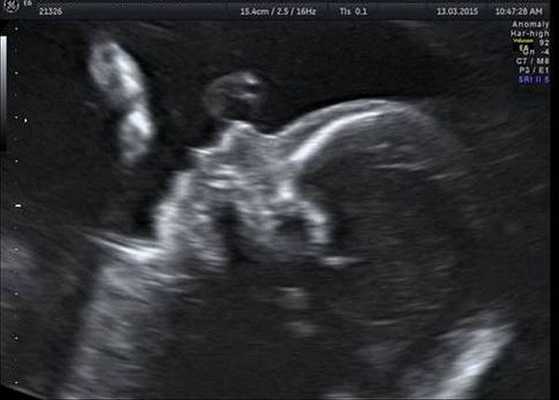

Формирование у плода заячьей губы можно заподозрить во время ультразвукового исследования уже на 14-16-й неделе беременности. У новорожденного младенца дефект заметен сразу.

По шкале влияния на формирование заячьей губы неблагоприятные факторы располагаются в следующей последовательности: химические (22,8%), психические (9%) механические травмы (6%), биологические (5%), физические (2%) и т. д. Определить рождение ребенка с заячьей губой можно по данным ультразвукового исследования плода на поздних этапах беременности. Родителям, уже имеющим ребенка с расщелиной губы, перед планированием следующей беременности показано медико-генетическое консультирование.

Врожденные аномалии лица в основном определяются еще в антенатальном периоде при плановом УЗ-скрининге беременной. При этом врач оценивает размеры и глубину поражения, чтобы заранее спланировать ход реконструктивной операции, скорректировать протокол ведения родов. При подозрении на сочетанные нарушения проводится амниоцентез, кордоцентез с последующей генетической диагностикой. В постнатальном периоде назначается полный комплекс обследований: